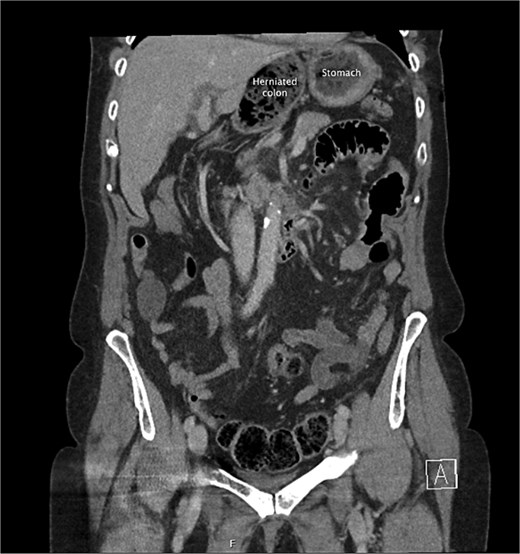

A coronal slice from the pre-operative CT abdomen pelvis in portal venous phase, with text labeling the herniated colon and differentiating this from the stomach.

She had a computed tomography (CT) abdomen and pelvis in the emergency department, which was initially reported as mesenteric panniculitis. She had an initial lactate of 3.3 mmol/l (reference range < 2.0), other blood tests, including white cell count and hemoglobin level, were normal. C-reactive protein was also normal. She was referred to the surgical team in the morning to determine a follow-up plan as her pain had improved and she was planned to be discharged home. On review by the surgical team, she was clinically well, her abdomen was soft and not tender on examination. However, on review of the CT images, there appeared to be a dilated segment of colon in the right upper quadrant, and on further analysis, it appeared to be a Foramen of Winslow hernia containing colon. There was also an area that appeared to demonstrate a potential filling defect in the portal vein along with periportal oedema. This raised the concern of a potential thrombus versus vascular congestion (Figs 1 and 2).